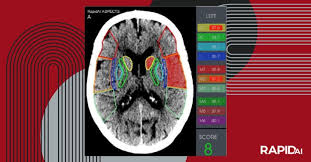

Với bệnh nhân nghi ngờ đột quỵ, việc đánh giá kịp thời bằng hình ảnh CT scan, MRI và các xét nghiệm khác có thể giúp xác định loại đột quỵ, đánh giá mức độ nghiêm trọng của tổn thương và định hướng quyết định điều trị. RapidAI là phần mềm ứng dụng trí tuệ nhân tạo hỗ trợ phân tích hình ảnh CT để hỗ trợ bác sĩ lâm sàng đánh giá các ca nghi ngờ đột quỵ, ngay cả khi bệnh nhân đến viện sau giờ vàng (4,5 giờ).

RAPID giúp phân tích hình ảnh y khoa như CT và MRI để xác định các vùng tổn thương não, tính toán thể tích khối máu tụ và vùng nhồi máu, từ đó giúp bác sĩ đưa ra quyết định điều trị chính xác và kịp thời, đặc biệt là mở rộng «thời gian vàng» điều trị lên tới 24 giờ thay vì chỉ 4 đến 6 giờ, trung bình 4,5 giờ, theo các phương pháp thông thường.

* Phân tích hình ảnh y khoa: RAPID sử dụng AI để phân tích nhanh chóng các hình ảnh CT và MRI não trong thời gian rất ngắn, chỉ từ 30 giây đến 2 phút và cung cấp kết quả phân tích chính xác về vị trí tổn thương, thể tích vùng não hoại tử và vùng não có nguy cơ bị tổn thương trong các giờ tiếp theo.

* Xác định vùng nhồi máu và thiếu máu: Phần mềm có thể định lượng chính xác thể tích vùng nhồi máu (vùng não đã chết) và vùng thiếu máu cần cứu chữa, là thông tin quan trọng cho việc quyết định can thiệp.